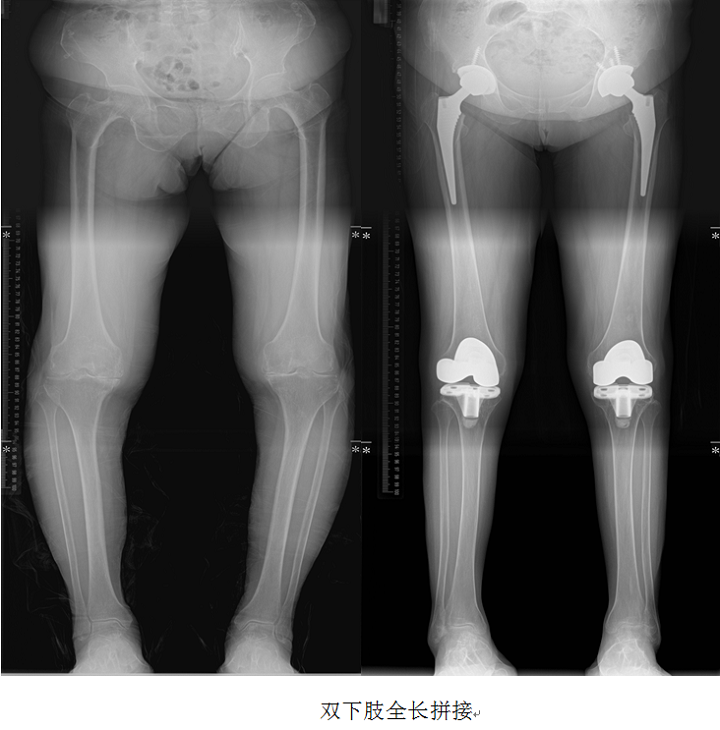

下肢全长拼接:

从髋关节到踝关节,采用3-4次分段曝光法采集信息,既可以全面观察骨与关节的形态、密度的改变,又可对生理角度(如髁-髋角、胫股机械轴夹角、平台-踝角等)、应力线等各种角度、径线进行测量。负重轴线的改变会使关节负荷分配线发生变化,影响关节负荷传导。如发生在膝关节会造成一侧关节软骨承受过大应力,导致软骨的逐渐磨损,引起膝关节炎。